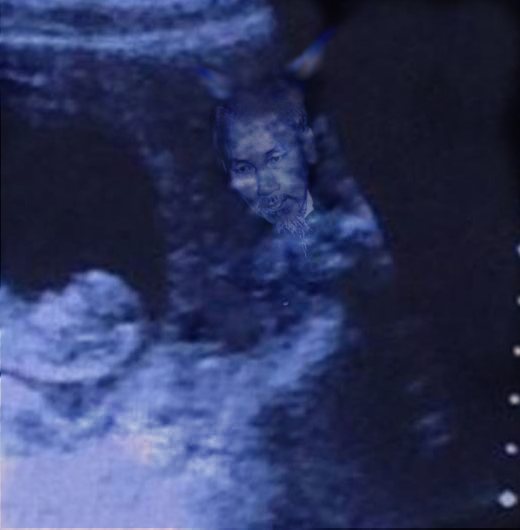

Mới đây, hình ảnh siêu âm thai của một người phụ nữ đã khiến cộng đồng mạng hoang mang tột độ. Cụ thể là trên bức ảnh đó bất ngờ xuất hiện hình ảnh giống như của “quỷ dữ” bên cạnh bào thai. Từ lúc bức ảnh được đăng tải trên mạng đã có rất nhiều luồng ý kiến trái chiều về hình ảnh của “quỷ” đó.

Thông thường, khi siêu âm người ta chỉ nhìn thấy em bé. Tuy nhiên mới đây, hình ảnh “quỷ dữ” xuất hiện trên màn hình bên cạnh thai nhi làm cho mọi người không khỏi giật mình. Nếu nhìn lướt qua, có thể nhiều người nghĩ đây là một bức ảnh siêu âm bình thường như bao ảnh siêu âm khác.

Theo tờ báo nổi tiếng của Anh Express mô tả, hình ảnh siêu âm có thể bình thường khi mới nhìn vào với thai nhi trong bào thai. Nhưng nếu quan sát kĩ hơn, nhất là ở góc phải, ta sẽ thấy hình ảnh của một người khác với khuôn mặt dữ tợn đang nhìn vào thai nhi.

Bức hình siêu âm này sau đó được đăng tải lên Imgur với chú thích: “Hình ảnh siêu âm thai nhi của một người bạn. Bạn thấy gì khi nhìn vào?”.

Với nội dung rùng rợn này, bức ảnh lập tức được phát tán một cách chóng mặt. Liên tiếp các bình luận được đưa ra. “Tôi thấy một con quỷ bên phải”, tài khoản Blind bình luận. “Không, nữ thần Hindu mới đúng chứ!”, bạn Lizzie cho biết. “Ủa sao tôi không thấy con quỷ nào nhỉ? Một nàng tiên cá thân thiện mà!”, một người khác phản bác.